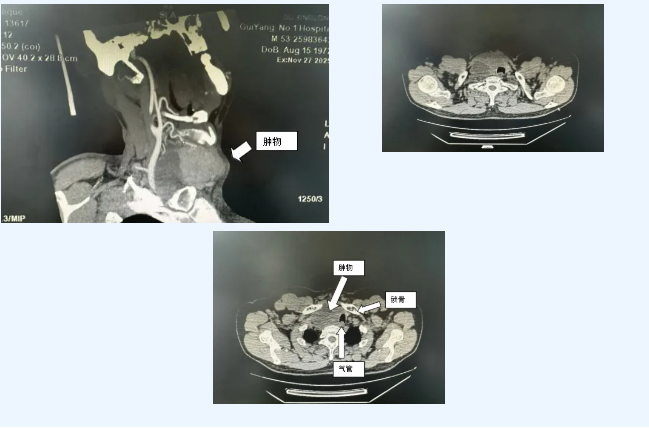

患者为中年男性,因“甲状腺右侧叶肿物切除术后复发1+年”入院。查体及影像学检查提示:甲状腺右叶区存在巨大(约8*9cm)、质硬、固定且边界不清的包块。经穿刺活检,病理确诊为“甲状腺乳头状癌并右颈淋巴结转移”。更为棘手的是,进一步评估发现,肿瘤范围广泛,已向下侵犯至胸腔入口,并与纵隔内重要血管结构关系密切、部分包绕,解剖层次紊乱。

由于肿瘤体积巨大、位置深在且固定,尤其已侵犯至颈部与胸腔交界的狭小区域,并与纵隔内关键血管结构粘连紧密,手术面临解剖复杂、操作空间受限、损伤重要结构风险高等严峻挑战,难度与风险极高。

鉴于肿瘤已超越常规颈部手术范围,侵犯纵隔,单纯颈部切口无法完整切除病灶并安全清扫转移淋巴结,经慎重讨论,最终确定了“双侧甲状腺全切除+双侧颈部淋巴结清扫+开胸纵隔淋巴结清扫”的联合手术方案。